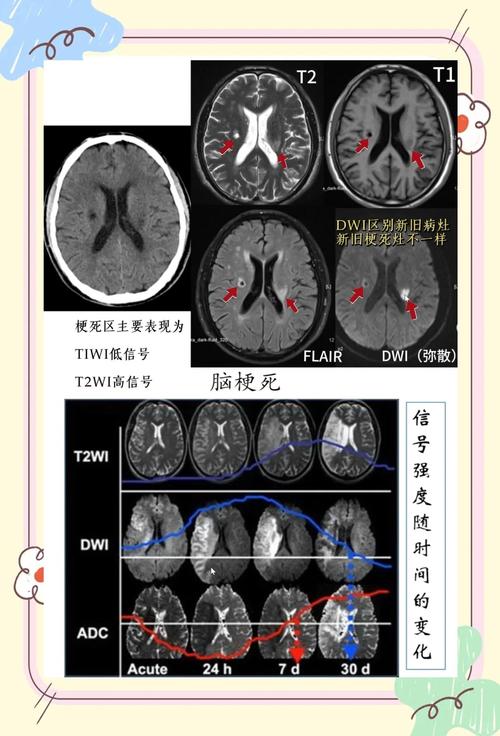

DWI可以在发病后数分钟内就发现缺血坏死的区域,比传统的CT和常规MRI(如T1、T2加权像)要早得多(通常早2-4小时)。 这为“时间窗”内的治疗提供了决定性的影像学依据。

当医生怀疑急性脑梗时,会开具头颅MRI检查,并特别关注DWI序列及其衍生序列ADC (Apparent Diffusion Coefficient)。

- DWI图像:在急性梗塞灶区域,会看到清晰、明亮的高信号(白色)病灶,这个病灶的大小和位置直接反映了缺血坏死的范围。

- ADC图像:这是DWI的“反向”图像,直接反映水分子扩散的程度,在急性梗塞灶,由于水分子扩散受限,ADC值会降低,因此在ADC图像上,同一个病灶会显示为低信号(黑色)。

“DWI高信号,ADC低信号”是急性期(超早期)脑梗塞的典型特征性表现,具有很高的特异性。

- 发病1-2周后:梗塞中心的脑细胞已经液化坏死,水分子又可以自由运动了,DWI上的高信号会逐渐消失,病灶可能变为等信号或低信号,而在T2/FLAIR序列上会变为永久性的高信号(软化灶)。

- 发病数周至数月:病灶进入慢性期,DWI通常为等信号,与周围脑组织难以区分。

- 在某些情况下,比如慢性、陈旧性的梗塞灶,在T2加权像上本身就是高信号,这种高信号也会“穿透”到DWI图像上,造成假阳性的假象。

- 鉴别方法:一定要看ADC图像,如果是T2穿透效应,ADC值是正常或增高的(在ADC图上是等信号或低信号),而真正的急性梗塞ADC值是降低的(在ADC图上是低信号)。